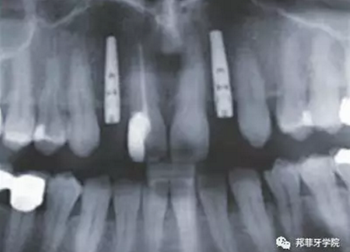

圖2:治療前全景片

采用手術(shù)導(dǎo)板進行備洞及植入,植入扭矩35Ncm。植體適當(dāng)偏腭側(cè)植入,避免鄰近結(jié)構(gòu)破壞及前庭處骨外壁穿孔。植體肩臺位于鄰牙釉牙本質(zhì)界根尖方2mm(圖7&8)。

牙齦成型器周圍應(yīng)嚴(yán)密縫合,防止唾液進入切口(圖9)。X線片顯示植體位置理想(圖10)。愈合期未見并發(fā)癥,植體周圍牙齦愈合良好(圖11)。十周后取模,椅旁制備臨時牙(圖12),并制作螺絲固位PEEK基臺。

圖 10:拍片復(fù)查植體位置